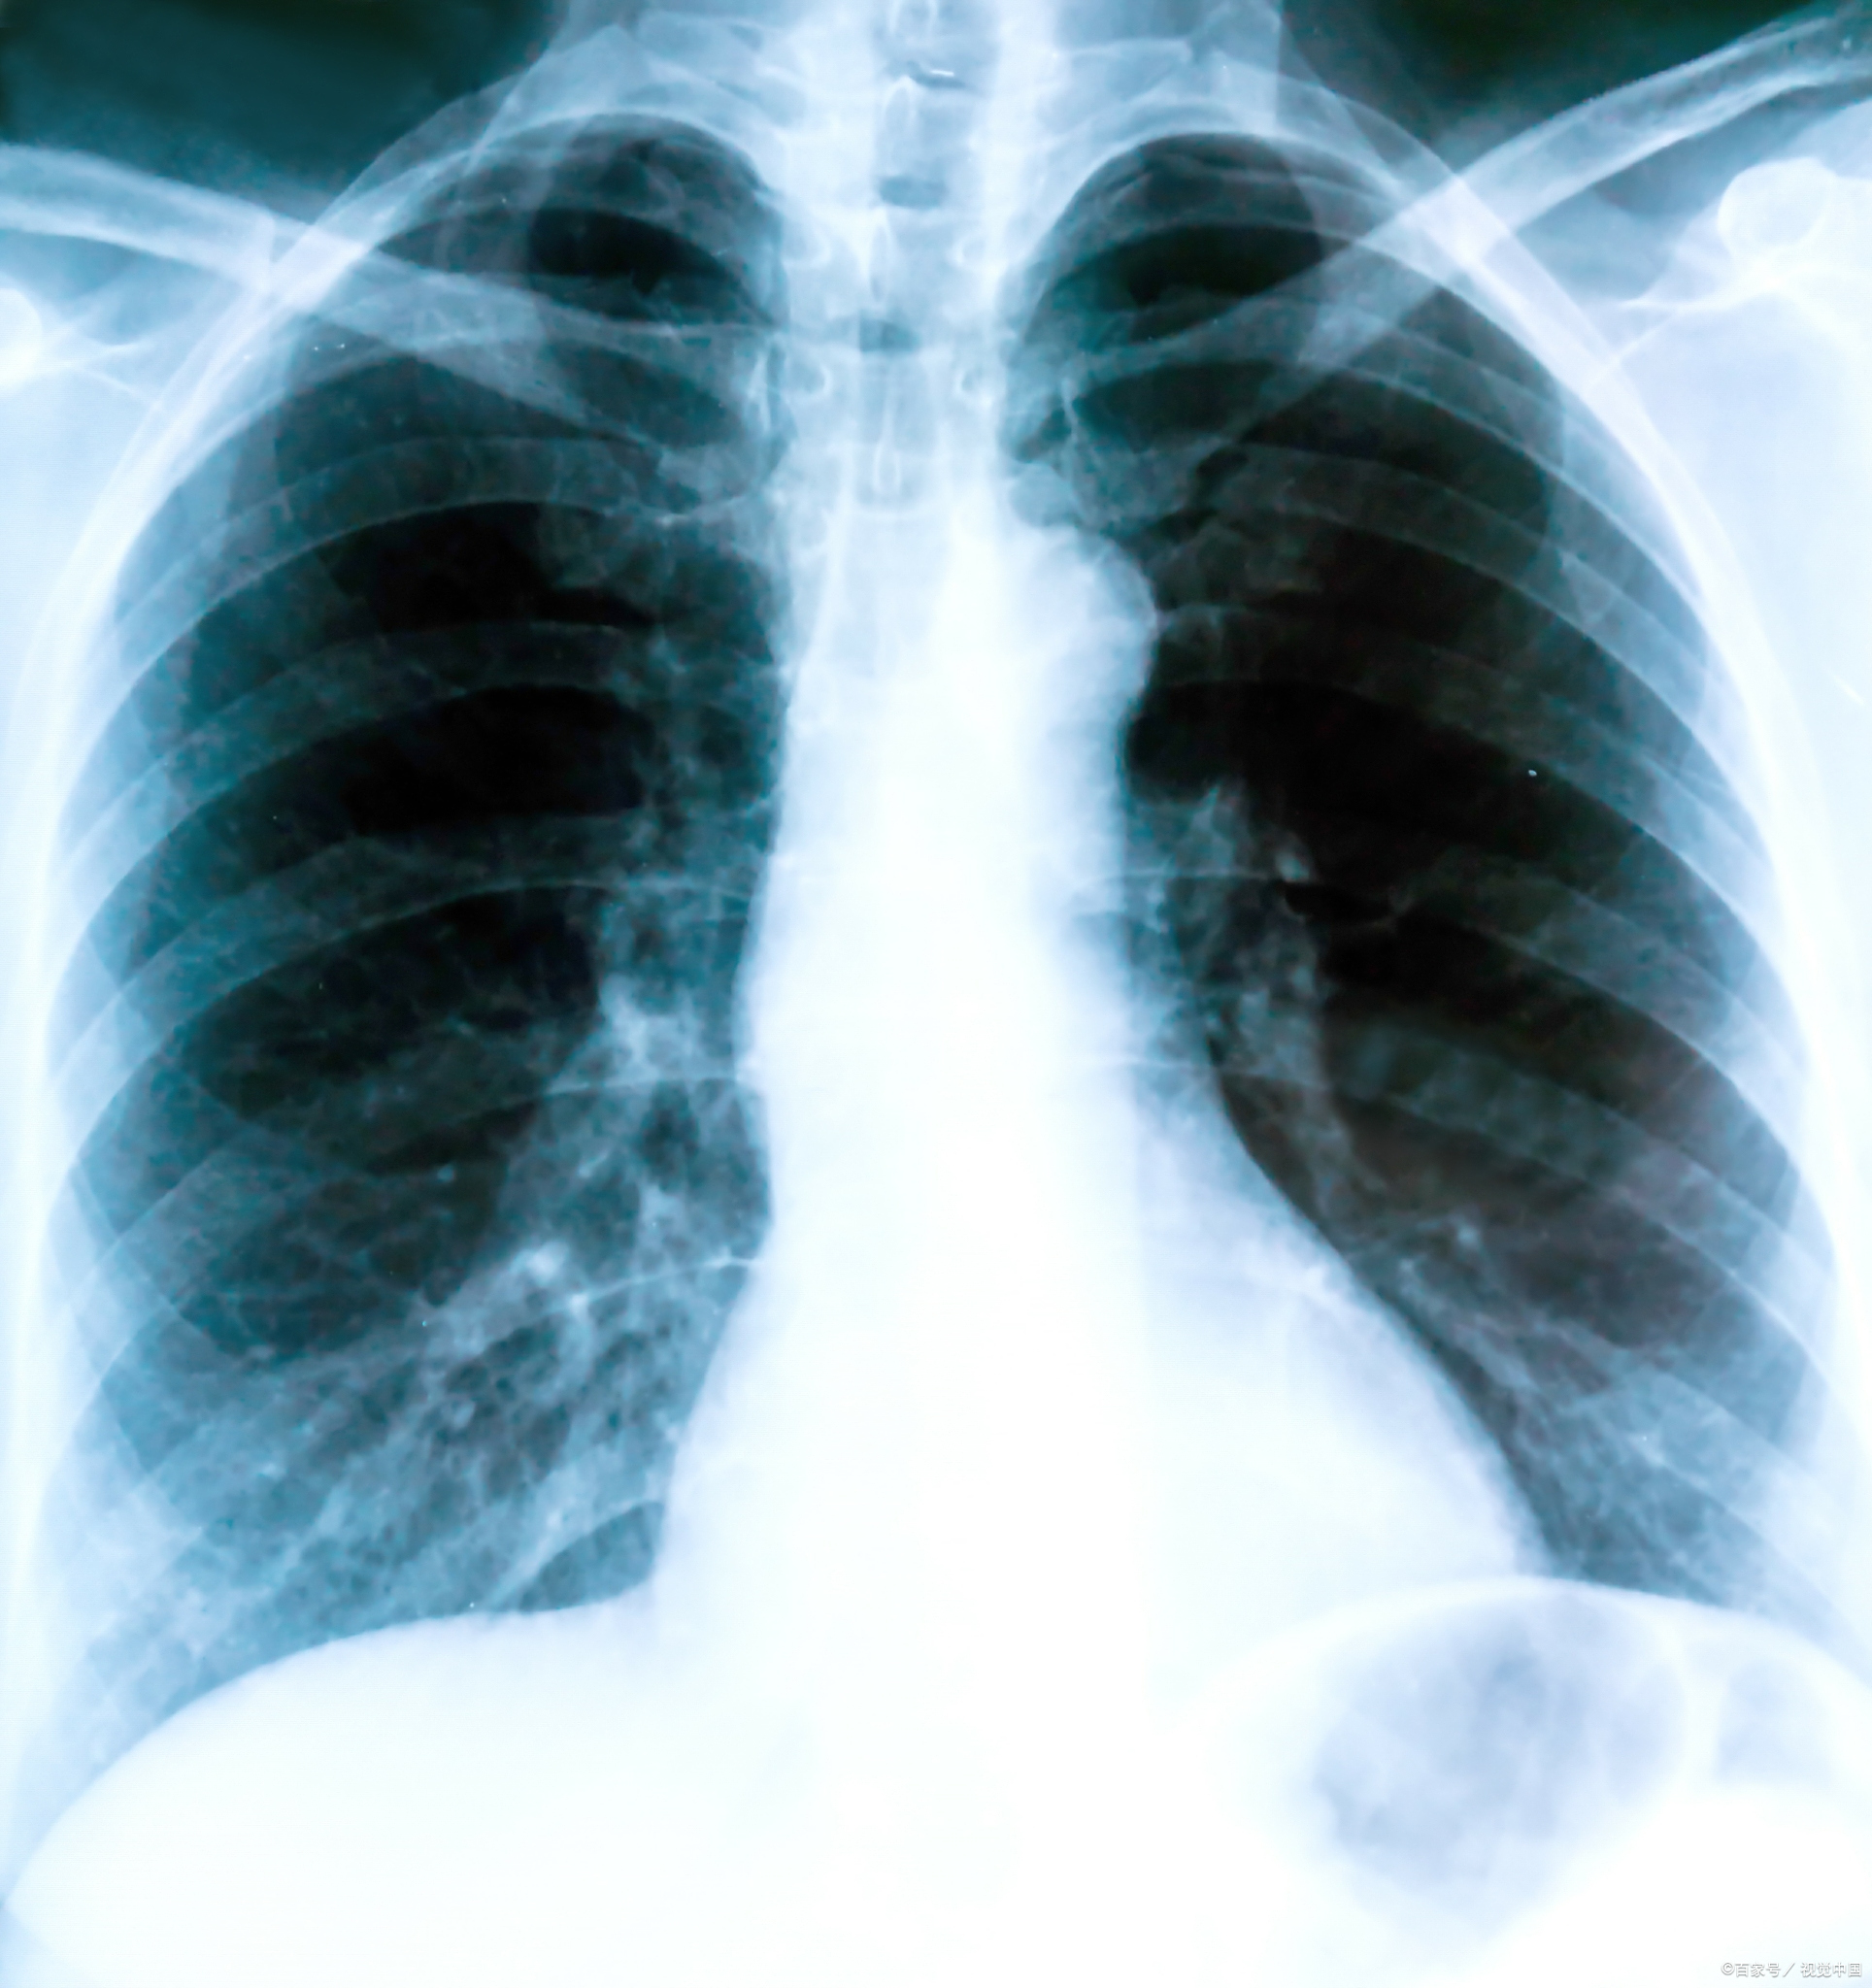

肺炎是呼吸系统常见疾病,而x光检查作为基础影像

一分钟教你看胸片,识别各种肺炎

最常见:肺部感染,炎症引发积液